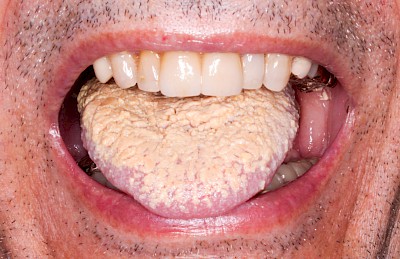

Pilzerkrankung / Belegte Zunge

Auf der Zungenoberseite (Zungenrücken) sind Pilzbesiedelungen häufig zu beobachten. Die gefruchte und zerklüftete Zungenoberfläche begünstigt das Wachstum von Pilzen. Vor allem bei eingeschränkter Zungenmobilität oder wenn wenige bzw. keine Zähne vorhanden sind, funktioniert die Selbstreinigung der Zunge nur noch unzureichend. Wird gleichzeitig kohlenhydratreiche pürierte Nahrung eingegeben sind die Wachstumsbedingungen für Pilze ideal. Hier kommt der gesonderten Zungenpflege mit speziellen Zungenreinigern oder einfach nur mit Zahnbürste und Zahnpasta besondere Bedeutung zu.

Beispiele20 Bilder